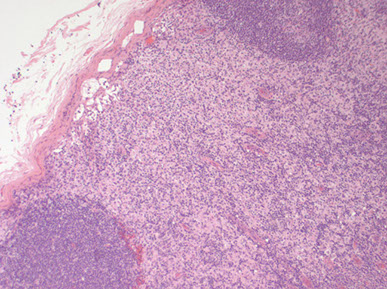

Reactive follicular hyperplasia (arrow to focal paracortical hyperplasia) [2]

Reactive Follicular Hyperplasia (RFH). Follicles (B-cell compartment) have varying size and are well spaced from one another. There is a nice capsule and subcapsular sinus. In medullary compartment where plasma cells and memory B-cell live, the sinuses are open and patent. Note the relative abundance of the paracortex compared to the cortex, which is an important feature for B9 LNs.